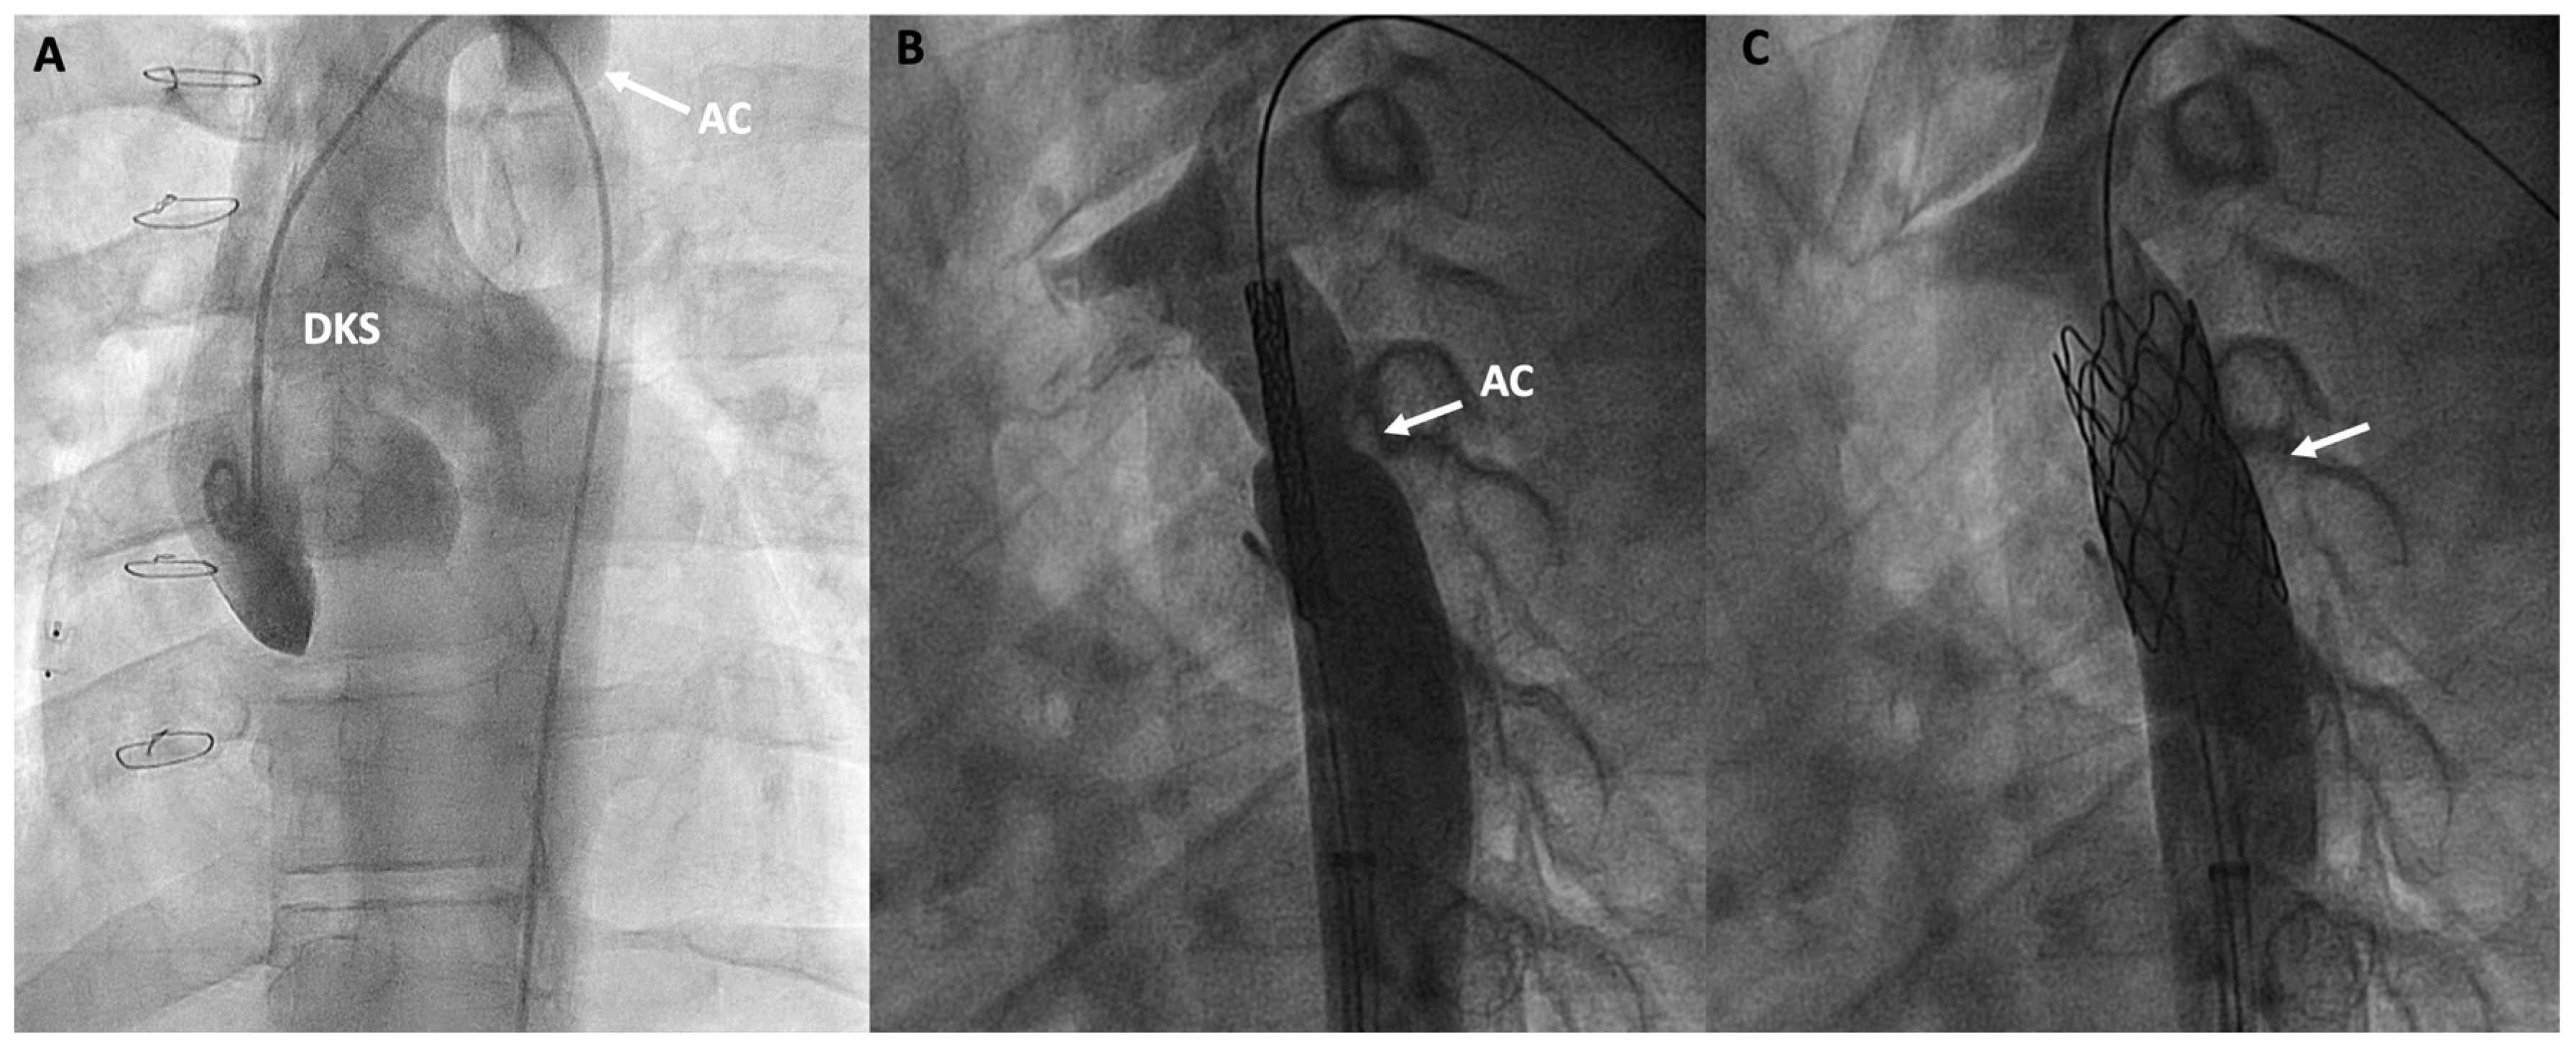

Figure 7.

Double inlet left ventricle, initially palliated with a Damus-Kaye-Stansel (DKS) procedure and subsequently with a Fontan procedure, presenting an invasive gradient of 18 mmHg in the thoracic aorta. (A) Angiographic image of the neoaorta in a patient with DKS with an associated aortic coarctation (AC) marked by an arrow; (B) Placement of a stent at the level of the coarctation (arrow); (C) Percutaneous repair of the AC after stent deployment (arrow).